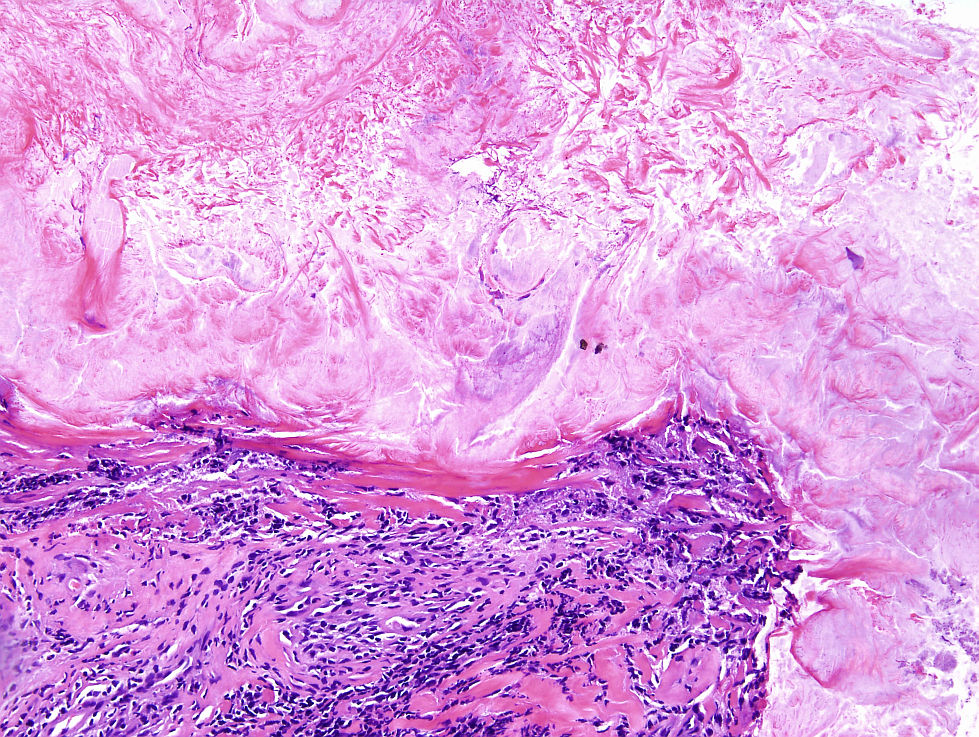

Cas dermatopatologia. Dona de 61 anys amb un àrea hiperqueratòsica vulvar

Març 2013

La biòpsia mostra una proliferació intraepitelial de cèl·lules de nuclis hipercromàtics i citoplasmes clars i abundants. A la porció més basal de dermis es disposen en grups, mentre que a dermis alta apareixen aïllades i són visibles fins i tot a la capa còrnia.